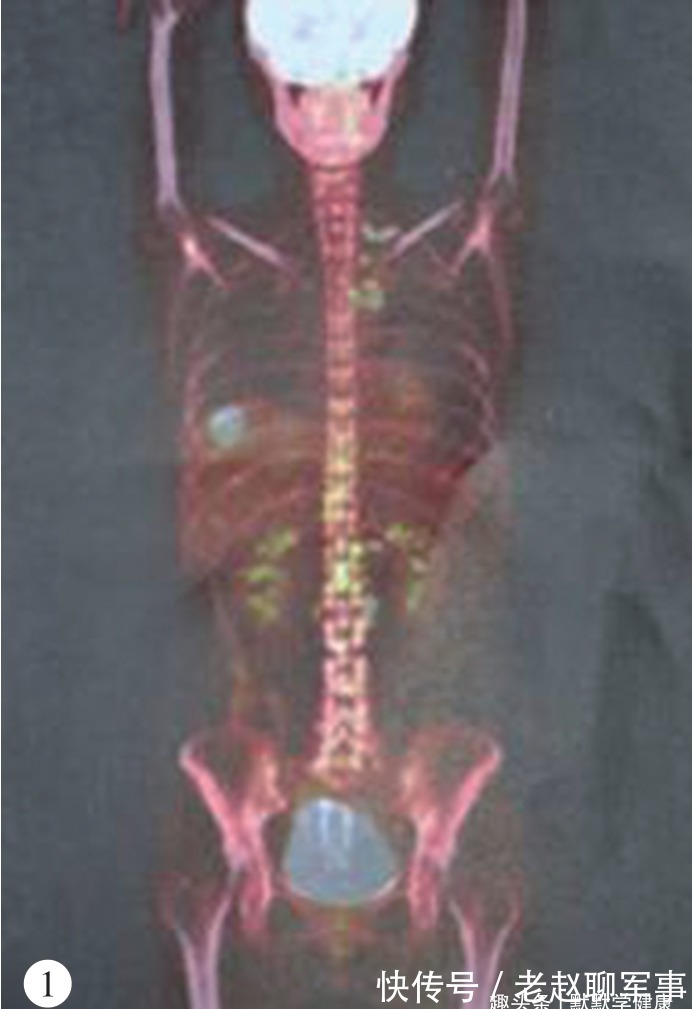

2014年5月,复查发现肿瘤标志物增高,PET-CT提示颈部、纵隔及腹腔多发淋巴结转移,肝转移,这一结果再次给了王兰一次“重击”,“看到结果的那一瞬间,真的想要放弃了,看不到希望”王兰忍不住回忆道。